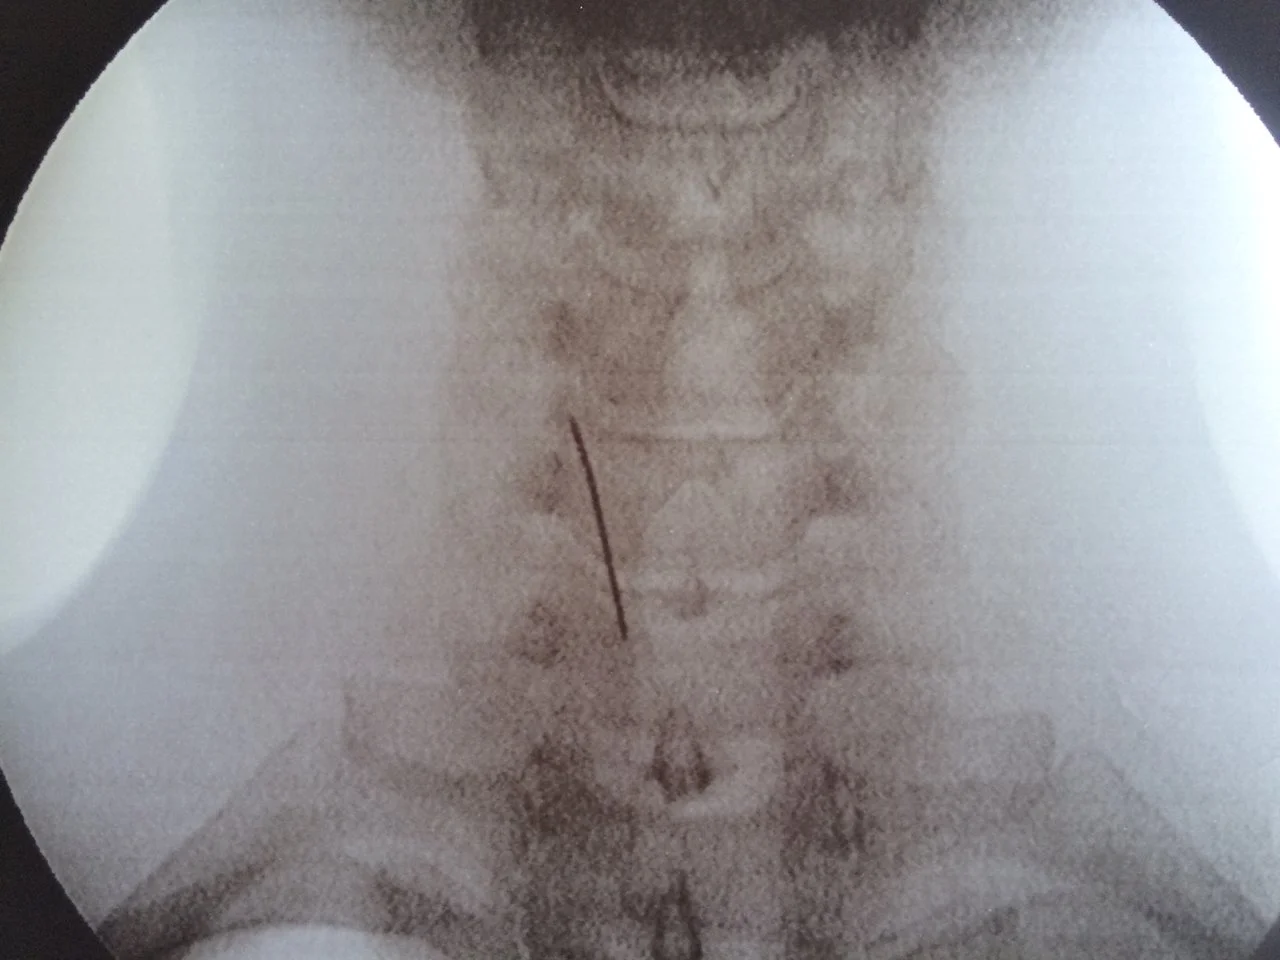

Da freue ich mich für Dich, dass Du's hinter Dir hast. War es denn erfolgreich? Und was will uns die Aufnahme sagen? Und was ist dieser schwarze Strich da an/in Deiner Hüfte?

Im Moment bin ich nahezu schmerzfrei, hoffentlich bleibt es so.Da freue ich mich für Dich, dass Du's hinter Dir hast. War es denn erfolgreich? Und was will uns die Aufnahme sagen? Und was ist dieser schwarze Strich da an/in Deiner Hüfte?![]()

die Kanüle, mit der sie das Zeug reingespritzt haben.![]()

...Heute noch einmal infiltrieren, und hinterher gleich ab nach Hause